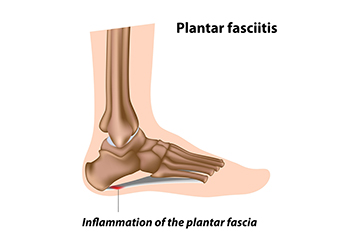

Plantar fasciitis is caused by inflammation of the plantar fascia, a thick band of tissue connecting the heel to the toes. Risk factors include obesity, prolonged standing, high impact activities, flat feet, high arches, and tight calf muscles. Symptoms often involve sharp heel pain, especially with the first steps in the morning or after periods of rest, as well as swelling and stiffness. Causes include overuse, poor footwear, sudden increases in activity, or biomechanical imbalances. A podiatrist can diagnose the condition, recommend supportive footwear or orthotics, provide stretching exercises, and offer treatments to reduce inflammation and restore mobility. If you have heel pain, it is strongly suggested that you promptly contact a podiatrist who can accurately diagnose and treat what may be going on.

What Is Plantar Fasciitis?

Plantar fasciitis is the inflammation of the thick band of tissue that runs along the bottom of your foot, known as the plantar fascia, and causes mild to severe heel pain.

The plantar fascia is a connective tissue in the heel that stretches across the bottom length of your foot. Plantar fasciitis occurs when the connective tissue becomes inflamed, causing heel pain and discomfort during physical activity. Although the condition is completely treatable, traditional methods can take up to a year to start becoming effective.

Plantar fasciitis is caused by a number of everyday activities, so understanding the condition is important for managing and treating it. One of the most common causes of plantar fasciitis is excessive running, especially with improper fitting or non-supportive shoes. Too much exercise can lead to the plantar fascia being overworked and overstretched, which can cause tears in the tissue. Along with improper fitting shoes, pronation, the rolling of the feet inward, is a common cause of plantar fasciitis. If not treated properly, the plantar fascia becomes overstretched and starts to tear, causing inflammation.